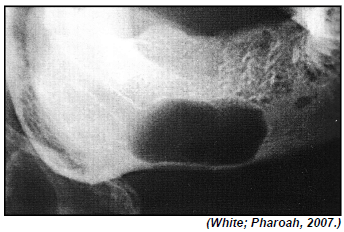

Durante a análise sistemática de imagens radiográficas de lesões intraósseas, a localização de seu epicentro e sua relação com estruturas anatômicas podem nos sugerir hipóteses de diagnóstico radiográfico.

A imagem radiográfica anterior pode indicar a ocorrência de